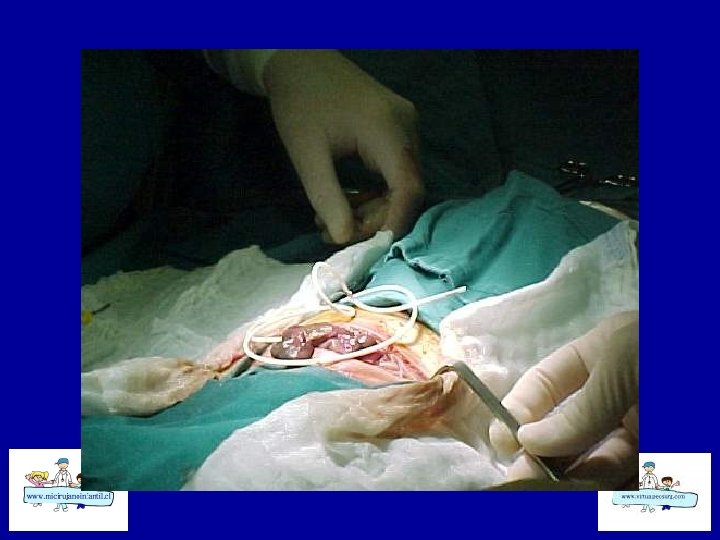

ECN-TRATAMIENTO • Quirúrgico: Laparotomías amplias • Drenaje peritoneal • Aseo abdominal y resección de asas necróticas • Ostomía vs Cierre primario • Second Loock

ECN-TRATAMIENTO • Cierre de derivación: desde 3 semanas a 10 meses. Según ubicación • Cierre precoz de ileostomía puede presentar complicaciones en la anastomosis, ECN recurrente del segmento distal. • Cierre Tardío: trastornos dérmicos y/o hidroelectrolíticos. • Siempre realizar estudio radiológico distal